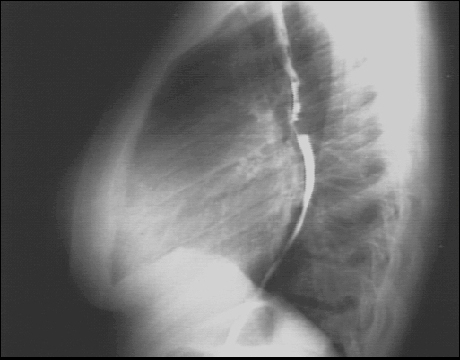

PA and Lateral

These are the PA and Lateral views of our patient's X rays for your intepretation

Click on the xrays to enlarge them.